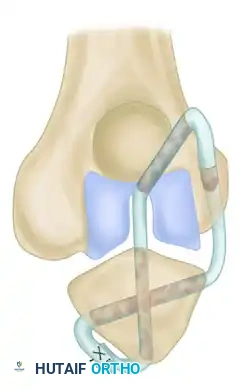

3. Ligament Reconstruction (The Arafiles Technique)

In cases of profound instability where dynamic fixation is unavailable or insufficient, surgeons may opt for ligament reconstruction with or without adjunctive fixation. The Arafiles technique utilizes a tendon graft routed through precisely drilled osseous tunnels to recreate the stabilizing vectors of the collateral ligaments.

The following sequence illustrates the complex reconstruction for an old posterior dislocation of the elbow, demonstrating the slot created in the trochlea and the specific lines of drill holes (A to D) that dictate the course of the tendon graft.

Note the intact forearm flexor origin during the completed repair, which provides secondary dynamic stability to the medial aspect of the reconstructed joint.